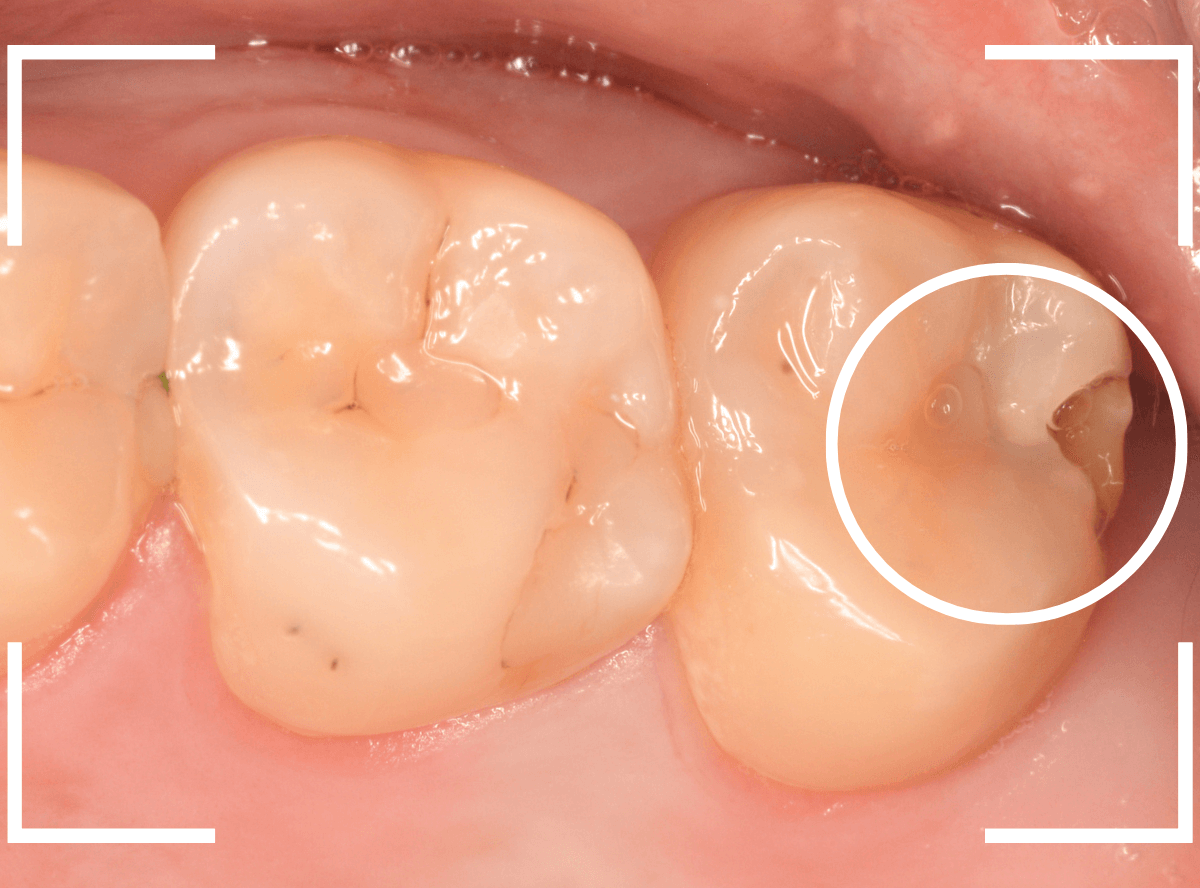

Case.12 下の一番奥の歯が、奥からひどい虫歯

「下の一番奥の歯が痛い」という訴えで来院された患者さんの例です。

一見では、特に問題ないように見えます。

レントゲン写真で確認します。

青いラインが歯の神経、赤いラインが虫歯です。

歯の奥の見えない部分から、大きな虫歯になっているのがわかります。

神経を除去しなければいけないかもしれないくらいの虫歯です。

治療を開始します。

歯の奥の部分を少し削ると、虫歯が出てきました。

慎重に虫歯を除去します。

歯肉ラインの下まで虫歯が進行しているため、虫歯の上に歯肉が広がっており、虫歯の見分けがつきづらい状況になっています。

虫歯を取り残さないように、余分な歯肉を除去します。

電気メスで、虫歯周囲の歯肉を除去後、全ての虫歯を除去しました。

虫歯は深かったですが、なんとか神経寸前のところで食い止められました。

神経を保護するお薬をつめて、セメントで蓋をしてしばらく経過観察します。

経過観察後、痛みがない事が確認できれば、つめものを作製します。